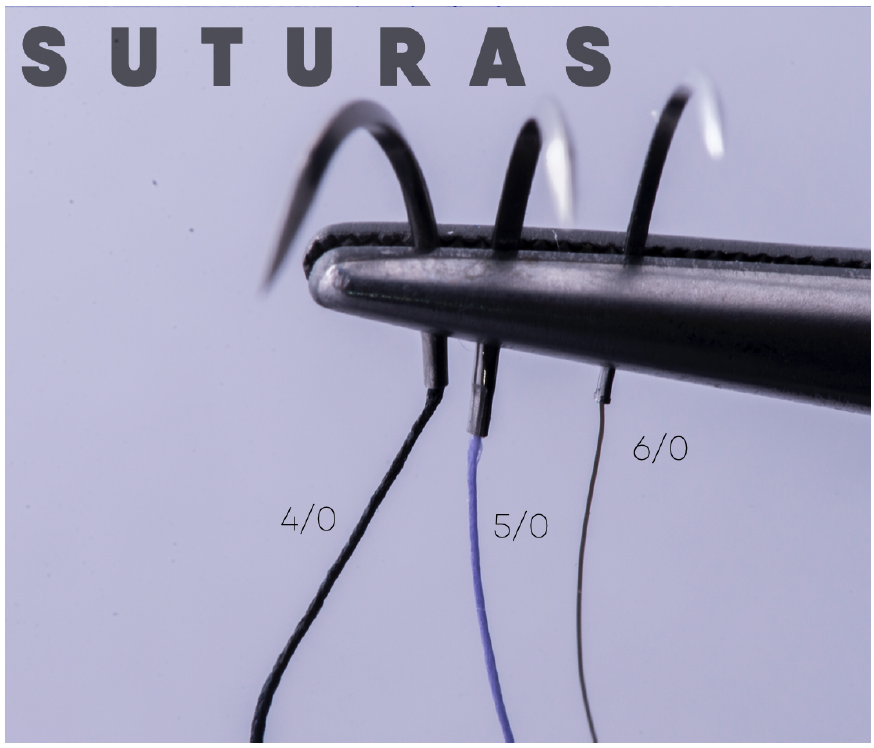

8. Sutura, comienza una nueva cirugía.

Cuando comienza la sutura del injerto y cierre del colgajo, mentalízate como si empezaras una nueva cirugía, cambia de guantes, organízate nuevamente, es muy probable que te encuentres un poco agotado, pero recuerda que la sutura influye mucho en el éxito del tratamiento, así que hazlo con paciencia y precisión.

Te sugiero utilices una sutura monofilamento, de calibre 6/0, longitud de diámetro no mayor a 15 mm y de corte reverso.